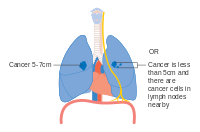

Staging[edit | edit source]

Lung cancer staging is an assessment of the degree of spread of the cancer from its original source.[77] It is one of the factors affecting both the prognosis and the potential treatment of lung cancer.[2][77]

The evaluation of non-small-cell lung carcinoma (NSCLC) staging uses the TNM classification (tumor, node, metastasis). This is based on the size of the primary tumor, lymph node involvement, and distant metastasis.[2]

T3 Any of: Tumor size more than 5 cm but less than or equal to 7 cm across

Invasion into the chest wall, phrenic nerve, or parietal pericardium

Separate tumor nodule in the same lobe

T4 Any of: Tumor size more than 7 cm

Invasion of the diaphragm, mediastinum, heart, great vessels, trachea, carina, recurrent laryngeal nerve, esophagus, or vertebral body

Separate tumor nodule in a different lobe of the same lung

Using the TNM descriptors, a group is assigned, ranging from occult cancer, through stages 0, IA (one-A), IB, IIA, IIB, IIIA, IIIB, and IV (four). This stage group assists with the choice of treatment and estimation of prognosis.[80]